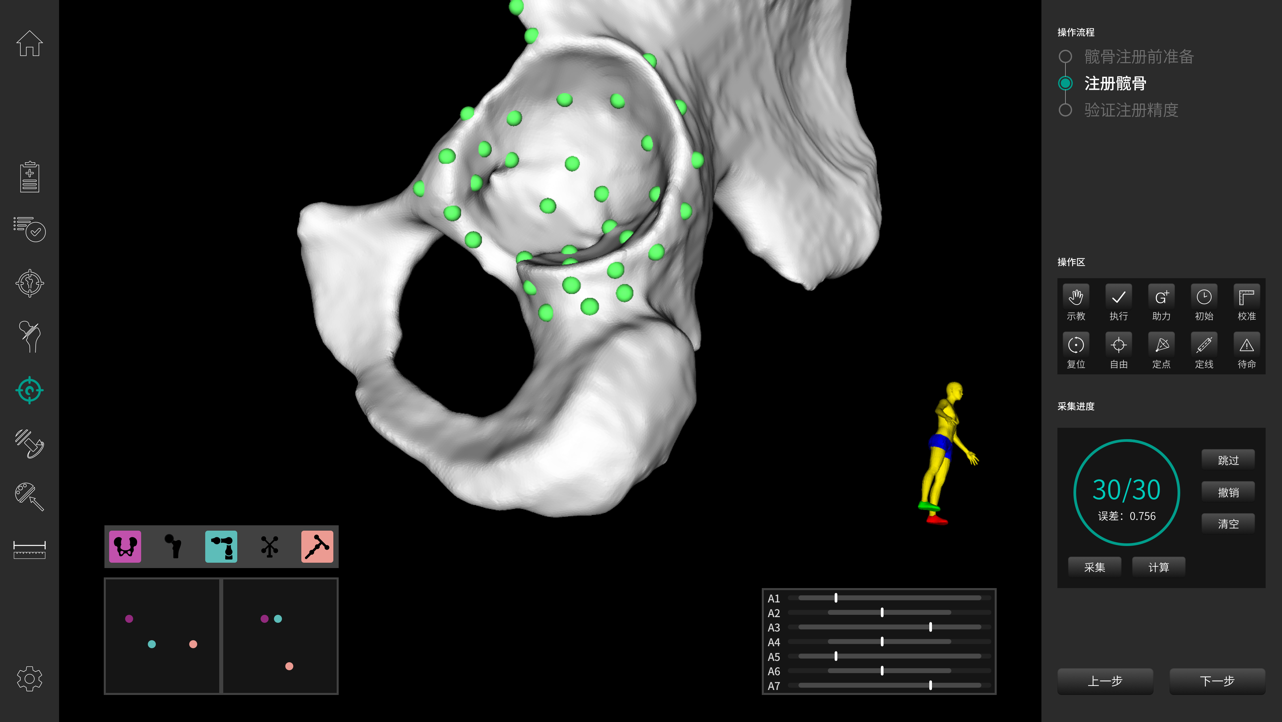

· 穩(wěn)定快速解剖點配準,將術(shù)中生理結(jié)構(gòu)與其術(shù)前影像數(shù)據(jù)建立空間關聯(lián),保證手術(shù)規(guī)劃的準確執(zhí)行。配準時間控制在3-5min。